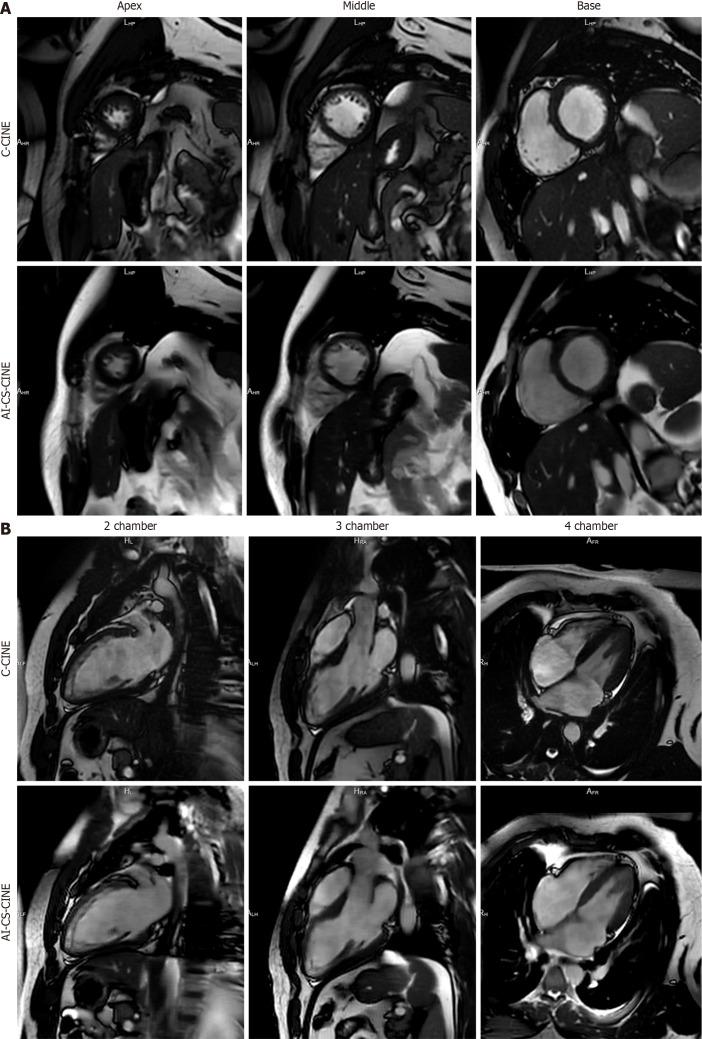

In 89 participants (58.5 ± 16.8 years, 42 males, 47 females), total AI-CS-CINE acquisition and reconstruction time (37 seconds) was 84% faster than C-CINE (238 seconds). C-CINE required repeats in 23% (20/89) of cases (approximately 8 minutes lost), while AI-CS-CINE only needed one repeat (1%; 2 seconds lost). AI-CS-CINE had slightly lower contrast but preserved structural clarity. Bland-Altman plots and ICC (0.73 ≤ ≤ 0.98) showed strong agreement for left ventricle (LV) and right ventricle (RV) metrics, including those in the cardiac amyloidosis subgroup ( = 31). AI-CS-CINE enabled faster, easier imaging in patients with claustrophobia, dyspnea, arrhythmias, or restlessness. Motion-artifacted C-CINE images were reliably interpreted from AI-CS-CINE.

AI-CS-CINE accelerated CMR image acquisition and reconstruction, preserved anatomical detail, and diminished impact of patient-related motion. Quantitative AI-CS-CINE metrics agreed closely with C-CINE in cardio-oncology patients, including the cardiac amyloidosis cohort, as well as healthy volunteers regardless of left and right ventricular size and function. AI-CS-CINE significantly enhanced CMR workflow, particularly in challenging cases. The strong analytical concordance underscores reliability and robustness of AI-CS-CINE as a valuable tool.